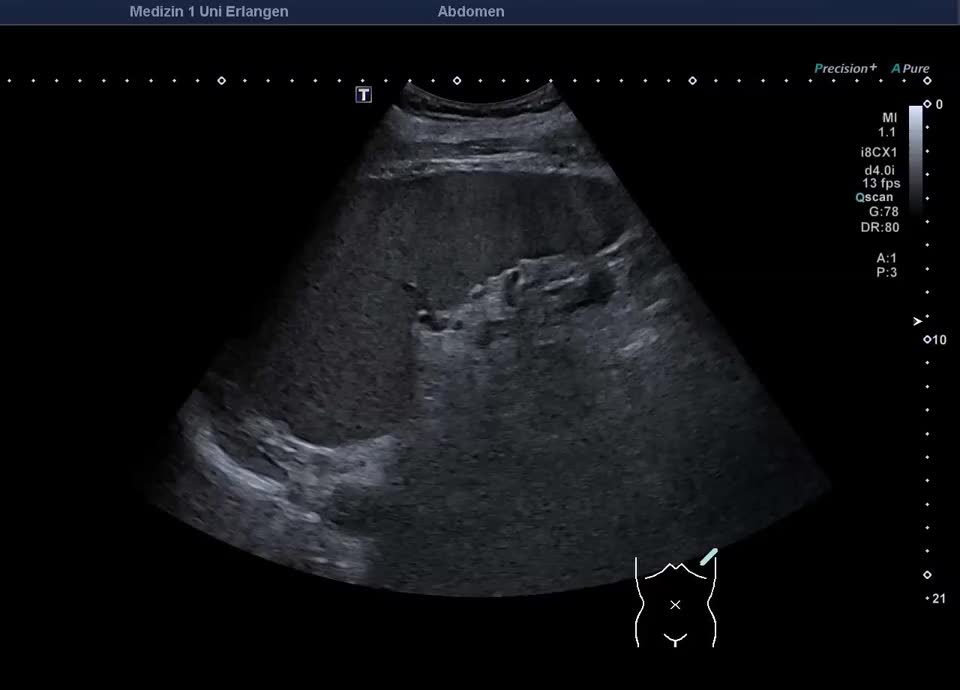

Splenomegalie